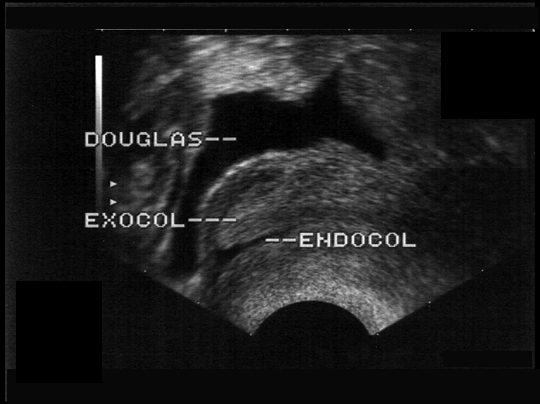

Défilé cervical normal. En phase ovulatoire la glaire cervicale est identifiée; le cul de sac de Douglas peut être le siège d'un épanchement minime.vv